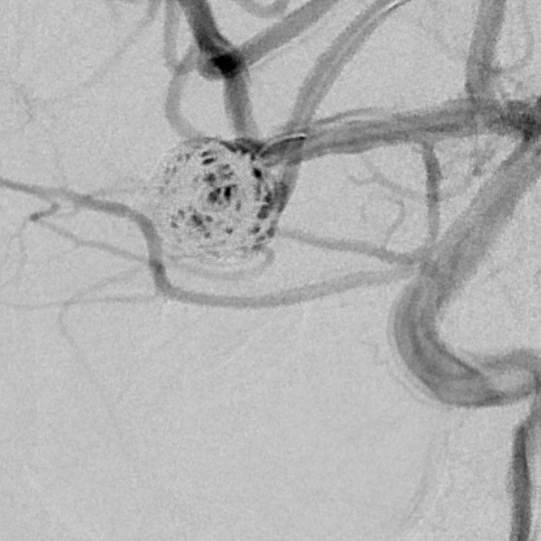

最终,动脉瘤瘤体致密栓塞,各个分支保留良好

粗大分支从破裂瘤体上发出来,急性期能单纯致密栓塞吗?